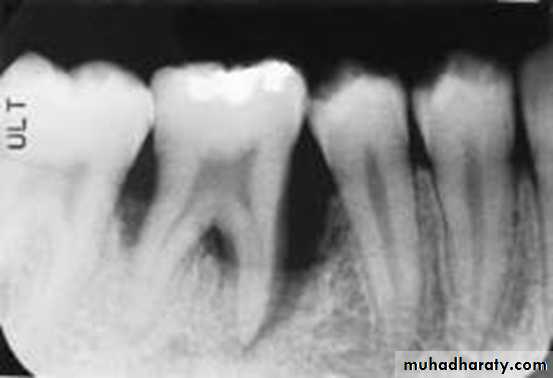

Periapical

Reproducible periapicals are the best for accurate diagnosis and clinical audit. Two radiographs at different angles may be essential to detect a root fracture. However, if access and cooperation are difficult, a single anterior occlusal radiograph rarely misses a root fracture. Periapical films positioned behind the lips can be used to detect foreign bodies.

Occlusal

This view detects root fractures when used inta-orally and foreign bodies within the soft tissues when held by the patient/helper at the side of the mouth in a lateral view.UNIVERSITY OF MOSUL